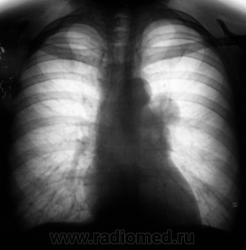

Две "флюшки"...

Слева флюорограмма за 2009 год, справа - сегодня...